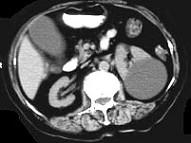

问题 女,38岁,左腰部胀痛不适,CT平扫+增强如图所示,下列说法正确的是 ( )

选项 A、考虑为左肾囊性肾癌 B、考虑为左肾囊肿 C、病灶边界清晰,表面光整 D、增强扫描皮质期和实质期该病灶均未见强化 E、平扫时可见左肾一类圆形囊性病灶

答案 BCDE